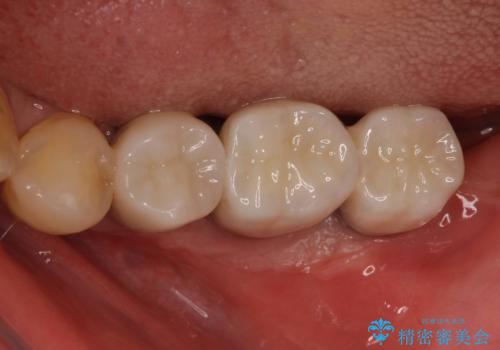

十分な角化歯肉が獲得でき、清掃性の高い環境が達成されました。